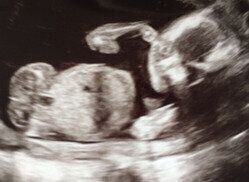

「妊娠36週目の健診の日、“母親の勘”としか言えないような、何とも表現できない悪い予感がしたんです。この日は超音波検査をする予定はなかったのですが、『どうしても超音波で赤ちゃんを見てほしい』と担当医に強く訴えました。

それほど言うなら・・・と超音波検査をしてくれた医師が、画像を見てがく然としているのがわかりました。

そして『重度の水頭症だから、すぐに大学病院を受診してください』と。

由夏理さんは、大学病院で再度超音波検査を受けました。

「私の専門は泌尿器外科で、夫は整形外科。脳神経領域の疾患のことは、2人とも医学部で習った程度のことしか知りません。でも、『脳内の30%が水で埋まっていて、脳の一部がよく見えない状況』という医師の説明は、画像を見れば明らかで、それが胎児に重大な影響を及ぼすことはもちろん理解できました。

赤ちゃんの脳内にたまった水が多すぎて、自然分娩だと脳内の圧力がどうなるかわからないから、妊娠38週目に帝王切開を行うという説明でした。しかも、出産時に最悪は死産もありうると告げられたのです」(由夏理さん)